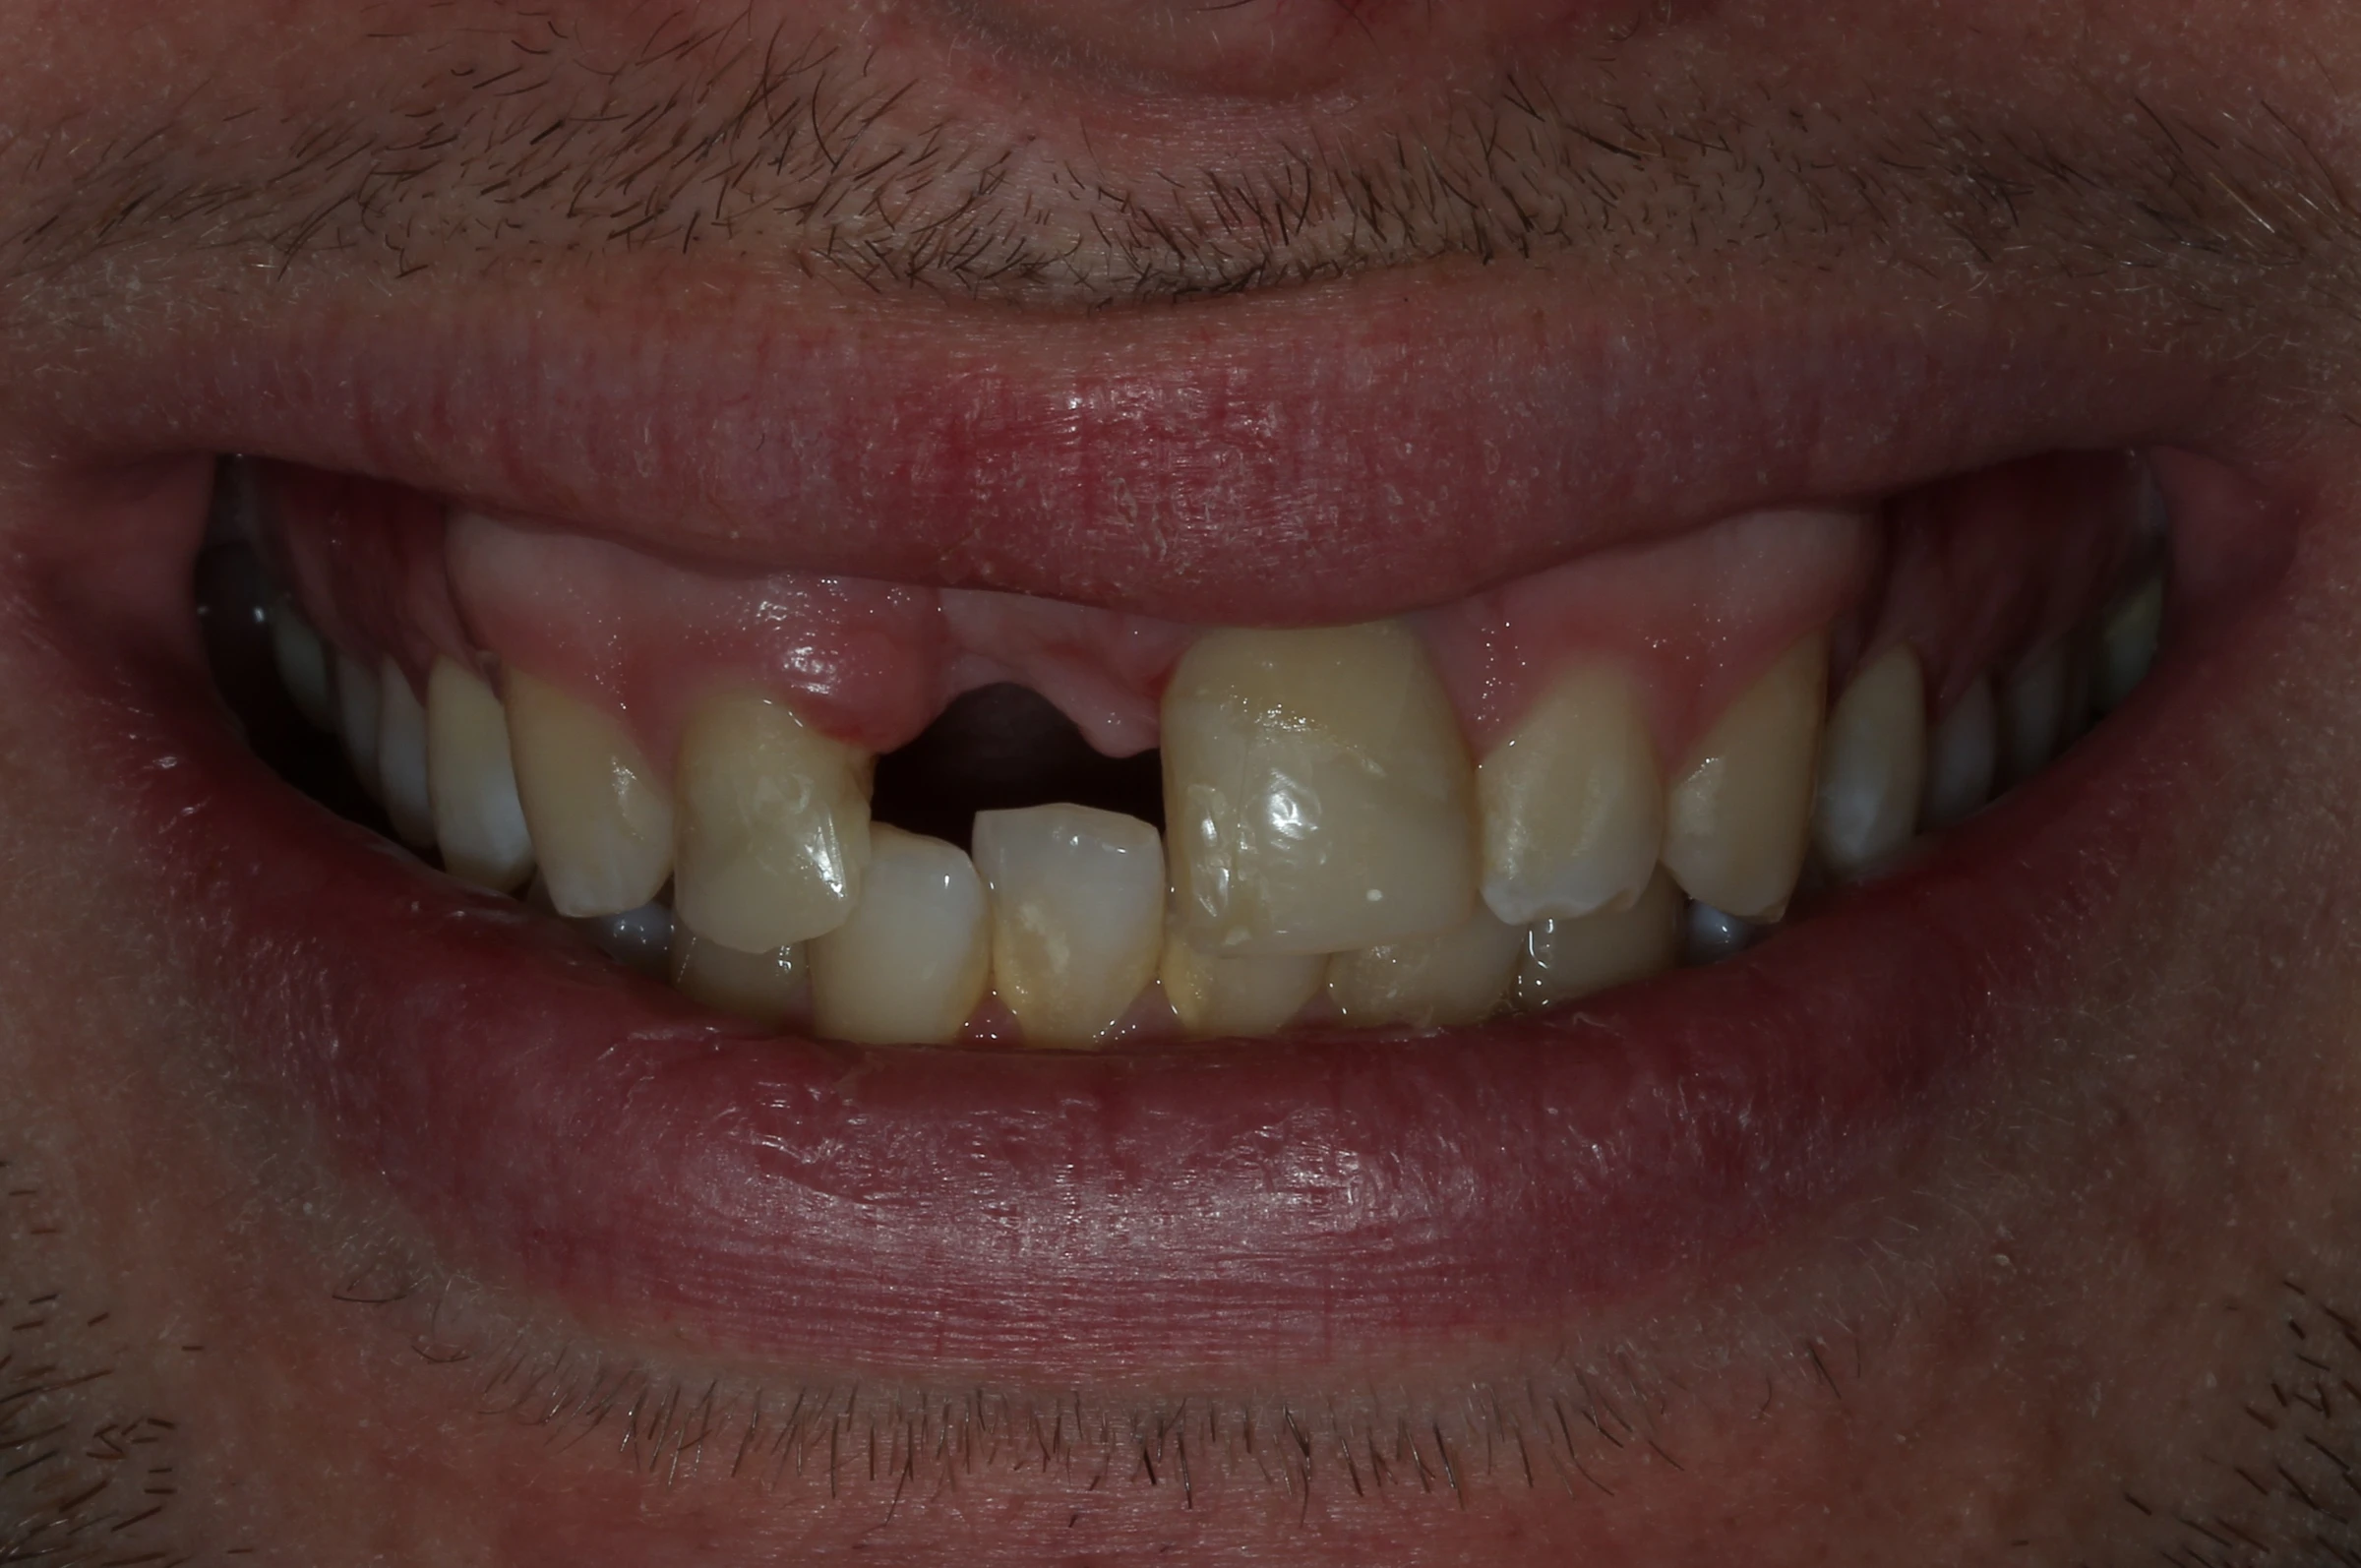

Alexei, un tânăr energic și activ, a suferit un accident în timpul unei vacanțe cu prietenii, în urma căruia a pierdut un incisiv superior central. Pe lângă impactul estetic major, trauma a dus și la pierdere de volum osos și gingival în zona afectată, ceea ce a făcut necesară o reabilitare implanto-protetică complexă.

Am pierdut un dinte frontal și nu mai îndrăznesc să zâmbesc. E prima dată când am o problemă atât de vizibilă și vreau să o rezolv cât mai natural cu putință.

Alexei, 29 ani

Pierderea incisivului frontal

Traumatism dentar cu avulsia completă a dintelui 21

Defect osos alveolar

Resorbție osoasă moderată în zona edentată

Impact estetic și funcțional

Dificultăți fonetice și disconfort estetic marcat